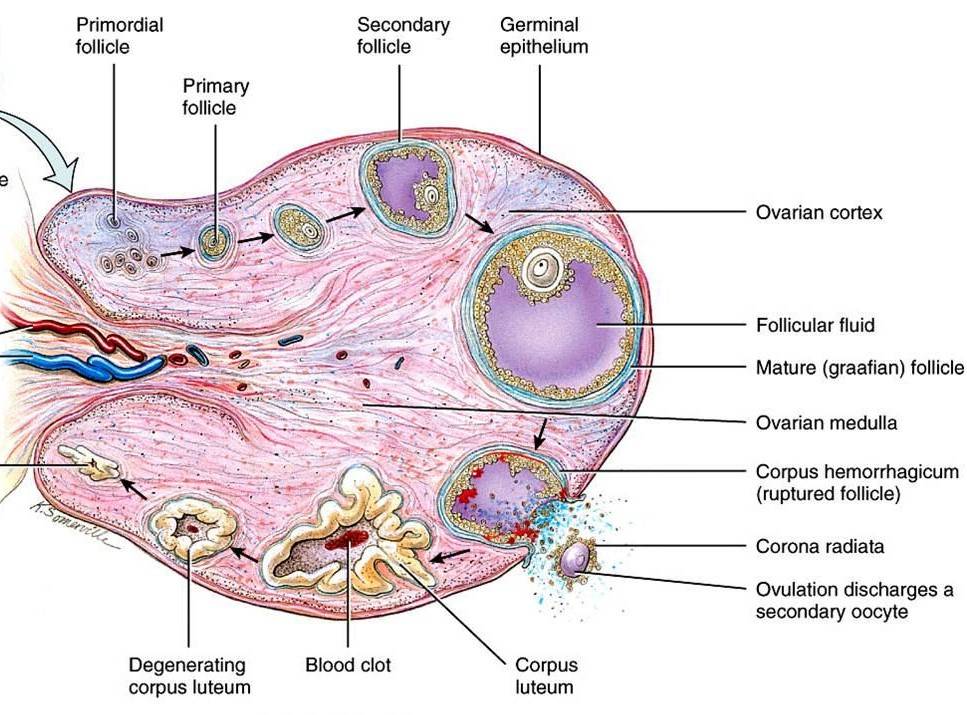

Созревание фолликула в яичнике: этапы и процессы